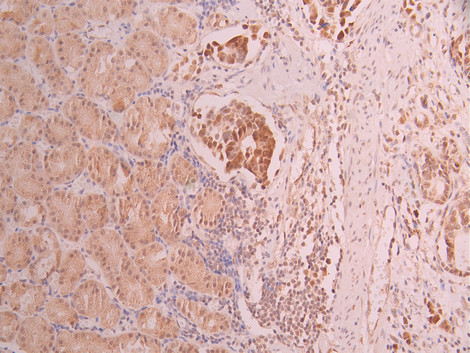

IHC image of CSB-RA172307A0HU diluted at 1:100 and staining in paraffin-embedded human gastric cancer performed on a Leica BondTM system. After dewaxing and hydration, antigen retrieval was mediated by high pressure in a citrate buffer (pH 6.0). Section was blocked with 10% normal goat serum 30min at RT. Then primary antibody (1% BSA) was incubated at 4°C overnight. The primary is detected by a Goat anti-rabbit polymer IgG labeled by HRP and visualized using 0.05% DAB.